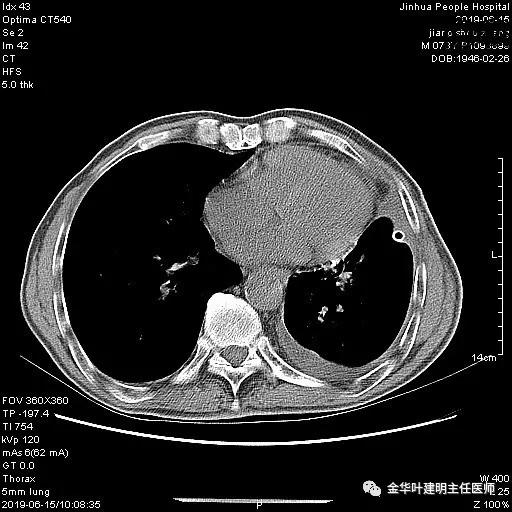

6.15上午:24小时胸管引流出血性液250ml;复查胸部CT示: